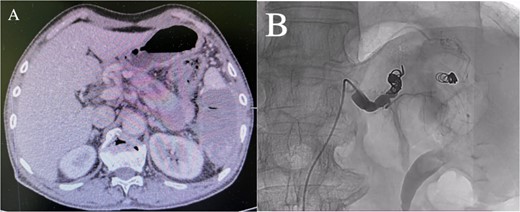

Enhanced CT showed regional portal hypertension and CP invading the splenic artery and forming a pseudoaneurysm of the splenic artery, partially invading the jejunum (Fig. 1A). Subsequent celiac angiography confirmed a pseudoaneurysm originating from the splenic artery (Fig. 1B). Combined with the characteristics of the patient’s history and the results of angiography, the patient was diagnosed with gastrointestinal bleeding: pseudoaneurysm of the splenic artery and CP. After excluding relevant contraindications, abdominal arteriography and embolization were performed simultaneously. So further intubation until confirmation of splenic artery angiography, we used a coil to embolize the pseudoaneurysm. At that time, repeat angiography showed that the main splenic artery and the pseudoaneurysm showed no further enhancement (Fig. 2B). Subsequent CT scan 6 days after the embolization showed no filling of the pseudoaneurysm (Fig. 2A), and he was discharged 2 days later. After 6 months of follow-up, the patient recovered well and returned to normal work and life.

(A) Abdominal CT scan 6 days after the embolization showed no filling of the pseudoaneurysm. (B) After embolization, re-examination showed that the main trunk of the splenic artery was accurately occluded, and the staining of the pseudoaneurysm of the splenic artery disappeared.